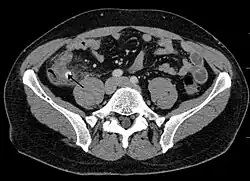

A fecalith is a stone made of feces. It is a hardening of feces into lumps of varying size and may occur anywhere in the intestinal tract but is typically found in the colon. It is also called appendicolith when it occurs in the appendix and is sometimes concurrent with appendicitis.[1] They can also obstruct diverticula. It can form secondary to fecal impaction. A fecaloma is a more severe form of fecal impaction, and a hardened fecaloma may be considered a giant fecalith. The term is from the Greek líthos=stone.[2]

A small fecalith is one cause of both appendicitis and acute diverticulitis.